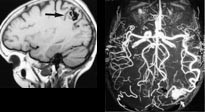

Ved arteriovenøse misdannelser kan MR bidra med kartlegging av relasjonene mellom misdannelsen og hjernens strukturer (fig 4). Dette vil ofte være helt avgjørende for valg av terapi. Hvis såkalt funksjonell MR også benyttes kan vi oftest forutsi hvilke strukturer og funksjoner som vil kunne bli skadelidende ved et inngrep.

I forbindelse med angiografiske utredninger er det ofte svært nyttig med MR-angiografi, f.eks. slik som vist i figur 4c, men ved en del problemstillinger er fortsatt deltaljfremstillingen ved MR-angiografi for dårlig. Digital subtraksjonsangiografi er foreløpig best når det gjelder å fremstille små detaljer og er et helt nødvendig hjelpemiddel ved intervensjonell nevroradiologi (28). Siden digital subtraksjonsangiografi er en invasiv metode og er potensielt farligere enn MR, vil det imidlertid ofte være naturlig å forsøke MR-angiografi først og deretter ev. supplere med digital subtraksjonsangiografi.